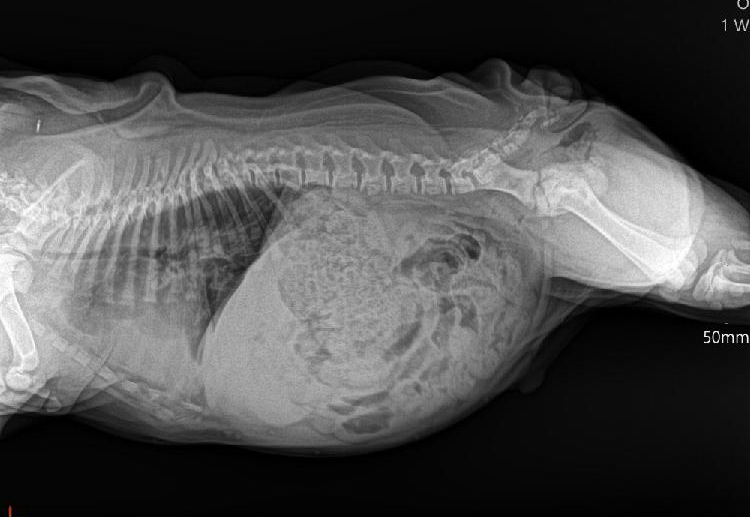

Dobrý den, chtěla bych Vás poprosit o konzultaci, prosím. Chceme si koupit štěně anglického buldoka, kterému je přes 4 měsíce, jako malý vdechl mlíčko, má nějaké problémy s průduškami- dle slov dr.:”patrný zástin v kranioventrálním úseku plicního pole, bronchovezikulární respirační šelest bez vrzotů, pískotů, atd. Máte s tím zkušenost, mám RTG snímky. Chtěla bych znát i druhý odborný názor.Myslíte, že je to vážné/může to mít následky do budoucna? Předem moc děkuji, hezký den.

Dobrý den, rtg snímek vypadá velmi závažně. Velká část plicních laloků je nevzdušná, ve spodní části hrudníku bych očekávala možná i volnou tekutinu. U tak mladého štěněte bych stav považovala za velmi závažný, samozřejmě s přihlédnutím ke klinickým projevům. V žádném případě ale nedoporučuji si štěňátko nyní kupovat bez dodiagnostikování a dořešení problému, může se jednat i o vrozenou vadu a nebo skutečně závažnější průběh infekce.